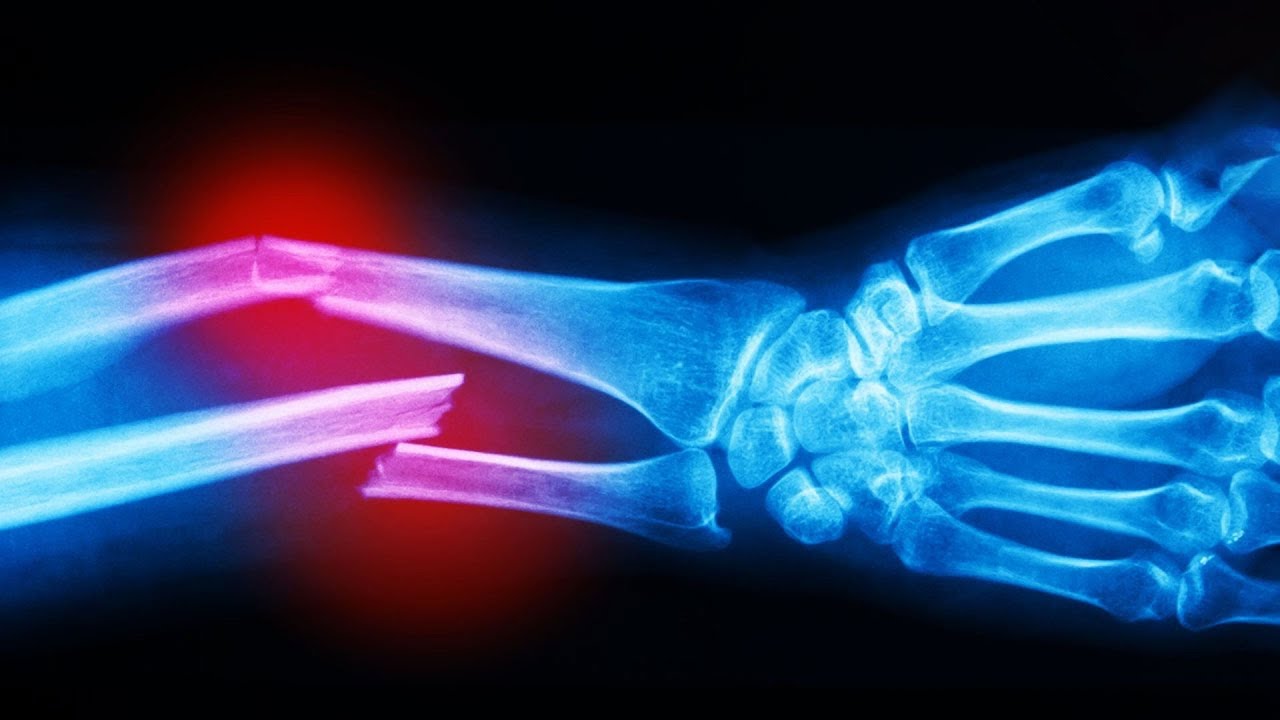

Мультяшные сломанные кости: Рисунки и комиксы

Раздел: Фотоархив